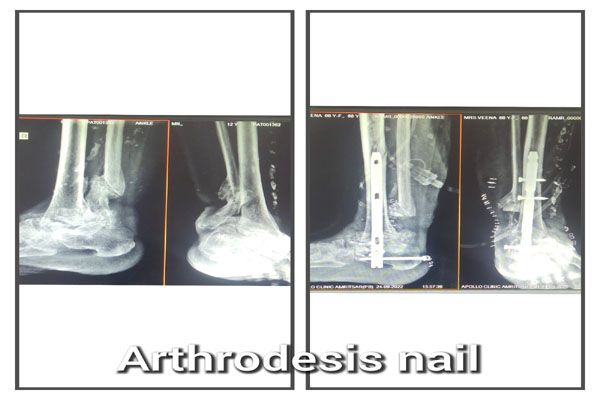

Fracture of bones is commonly handled by almost all orthopaedic surgeons in India. But dealing with comminuted intra-articular fractures (involving joints) is a night mare for most of them. It requires special expertise and experience to deal with such kind fractures. It can involve pelvic acetabular fracture, upper portion of thigh bone ( hip), lower portion of thigh bone ( femur), upper portion of arm bone (humerus head), lower portion of arm bone (humerus), lower portion of forarm bone (lower end of radius) fracture of heel bone, etc. The idea is to maintain the joint (articular) integrity and prevent the permanent loss of movements at that joint. It requires image intensifier (c-arm) to do these surgeries. May be artificial bone or autograft (patient’s own bone taken from iliac bone) to fill in the bone defect/ loss if present. The fracture may take 2- 3 months to heal. Patient may require prolonged physiotherapy to gain near normal range of motion exercises.